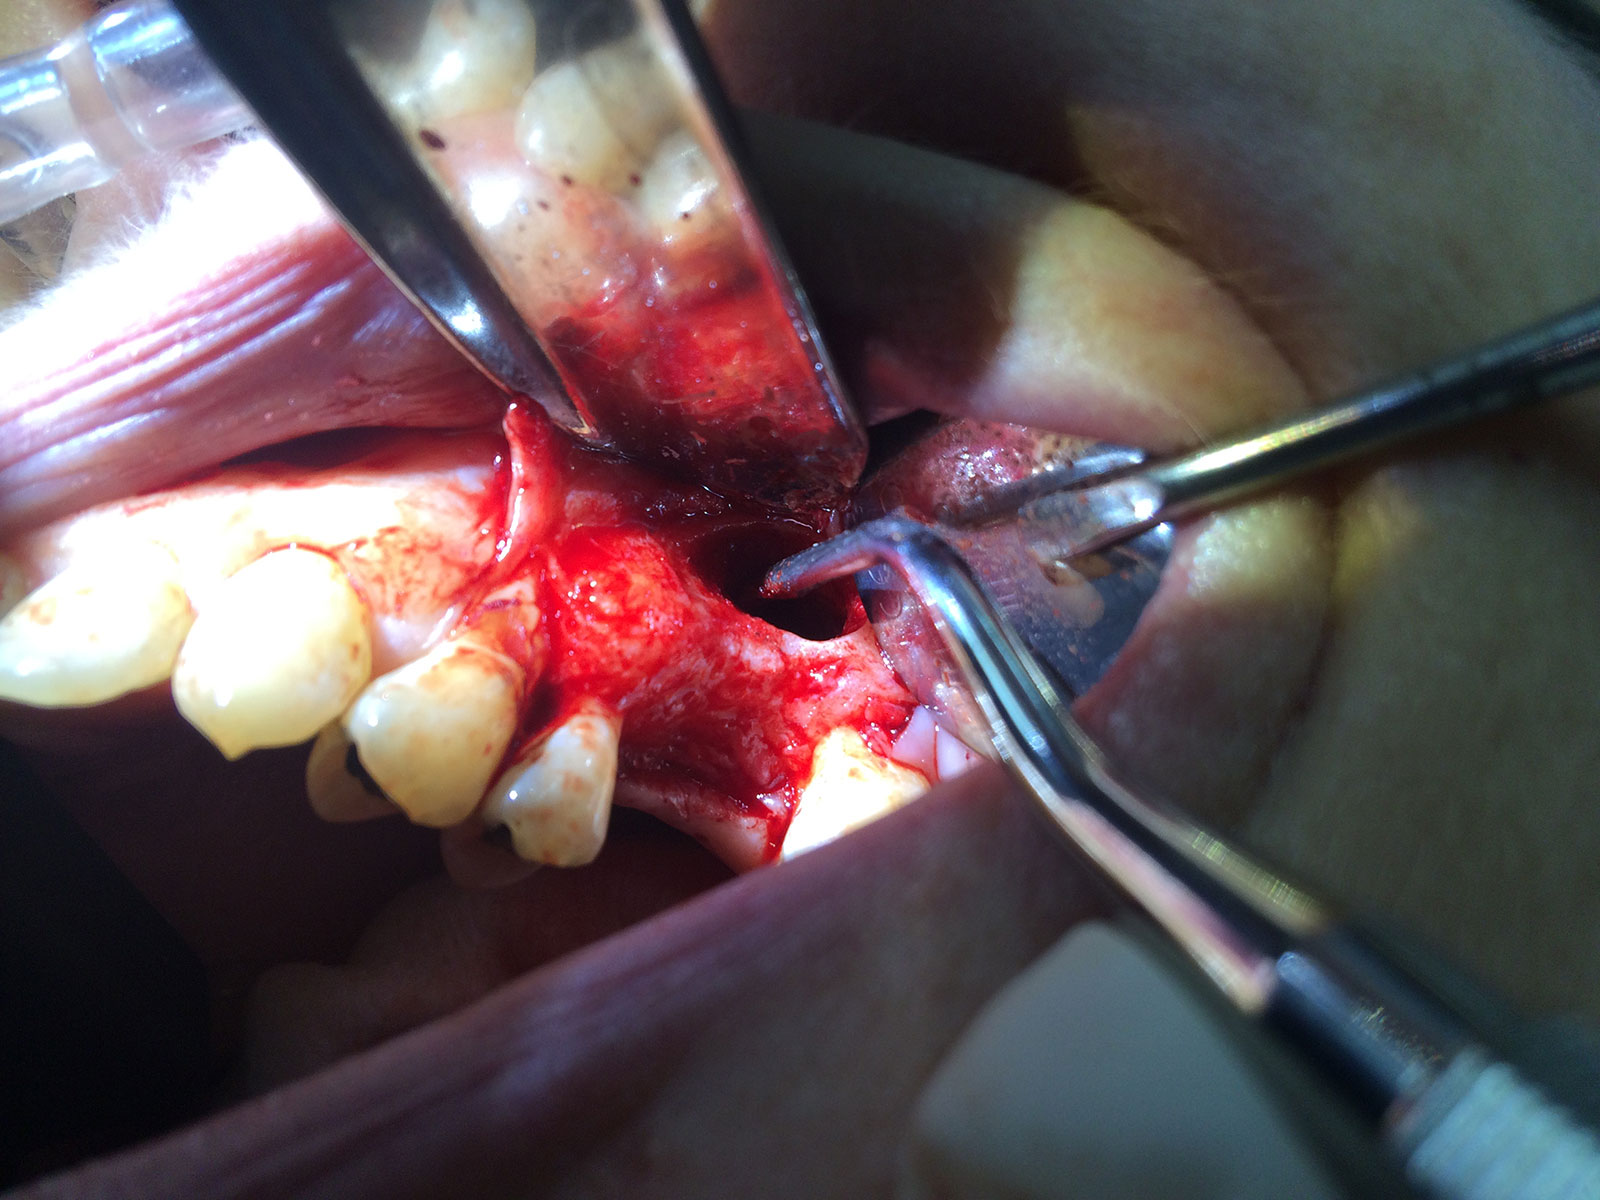

Sinus Grafting Procedures

A sinus grafting procedure, also known as a sinus augmentation, is for patients who have insufficient natural bone in the areas where dental implants are needed. They are long lasting, strong and sturdy, and fit and function like natural teeth. The procedure involves adding bone, either your own natural bone from another part of the body, from a donor or made of processed or synthetic bone material, and placing it below the sinus so that the implants can be placed. After the bone has healed and developed, usually around four to 12 months, the dental implants can be placed.

The photos on this website are from real surgeries performed by Dr. Ulloa. Due to the

graphic nature of the images and content, viewer discretion is advised.